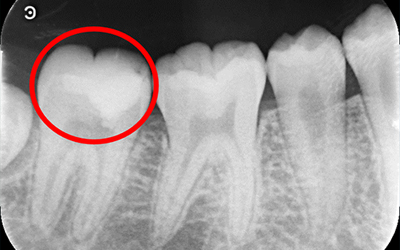

従来は、虫歯除去中に神経が見えてしまった場合は、無菌状態の神経が汚染されたと考えるのが一般的でした。

そのため、患者さん本人の痛みなどの自覚症状が無かった場合でも神経の治療をしなければなりませんでした。

しかし、現在の歯科医療では、すべての場合ではありませんが、神経を取らずに治療することができます。

それが「生活歯髄療法(VPT)」(バイタルパルプセラピー)です。

マイクロスコープで直接神経の状態を確認することです。

ポルトランドセメントを主成分とする薬で、このセメントを使う事により本来なら神経を取らざる得ない場合でも神経の保存が可能になりました。

| 注意事項 | MTAによる生活歯髄療法の適用と診断したが、すべての症例で歯髄保存が必ずしも成功出来るわけではありません |